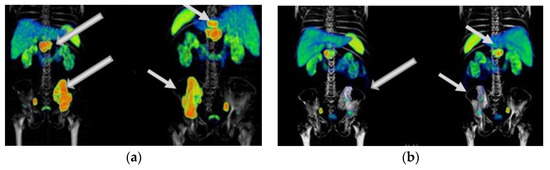

Figure A1. Patient with mCRPC who had a partial response to 177Lu-iPSMA treatment: (a) anterior and posterior 68Ga-iPSMA imaging before 177Lu-iPSMA treatment, and (b) after 177Lu-iPSMA therapy (four doses of 7.4 GBq). Arrows indicate tumor lesion sites.

177Lu-iPSMA therapy is a convenient option for the treatment of multiple metastases and large tumor lesions (Appendix A) (Figure A1, Figure A2 and Figure A3). For example, in the case shown in Figure A1, the patient suffered from severe pain characteristic of the terminal stage of the disease. However, two weeks after administration of the first dose of 177Lu-iPSMA, the subject showed relevant pain relief. Furthermore, after administering four doses of 177Lu-iPSMA (four doses of 7.4 GBq), metastatic lesions in the hip and spine were significantly reduced, prolonging the patient’s life for 19 months after therapy. In this context and based on the results of this study, 177Lu-iPSMA therapy should be considered and evaluated in future clinical trials as a second-line rather than third- or fourth-line therapy in patients with mCRPC, with the potential to improve patient survival.